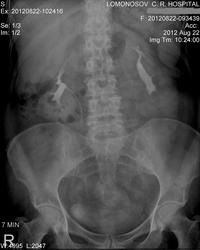

Размер левой почки представляется обычным, просто на ее тень наложилась тень кишечника. Нефроптоз по анатомическим границам есть, но не катастрофа. Что же касается полостной системы слева-по УЗИ нет никакой большой кисты, что может так оттеснять и чашечки и шейки?

Очень похоже на неполный поворот левой почки. Согласно Пытелю, лоханки в норме расположены на уровне L3. Кроме того, нефроптоз при смещении почек на высоту одного позвонка (согласно Пытелю), а по военному приказу - на два позвонка.

Справа отшнурована верхняя чашечка - синдром Фролея (добавочный верхнеполярный сосуд). Может иногда давать микрогематурию. Нефроптоз 1ст.

Слева - почка ротирована, мочеточник отходит от передней поверхности лоханки. В положении стоя в лоханочно-мочеточниковом сегменте определяется перетяжка, обусловленная, вероятнее всего, добавочным нижнеполярным сосудом. Это может привести к пиелоэктазии. Думаю, если б пациентка постояла еще минут 10, а потом сделать снимок, то пиелоэктазия была б более выраженная. Камней в мочеточнике, скорее всего, нет. Они контрастируются цистоидами, т.е. перистальтика их никак не нарушена. Даже небольшой рентгенонегативный камень дал бы косвенные симптомы нарушения пассажа мочи.

Левая почка представляется увеличенной, но размеры надо померить. ЧЛС деформирована… ригидность какая-то. Множеств. кисты? Подумалось о туберкулёзе. Томография на универсальном телеуправляемом штативе с цифровым детектором – простая ведь процедура. Надо было сделать. Возможно, и камень нашёлся бы. Нефроптоз несущественный.

Кисты почек хорошо видны на УЗИ, поэтому томографировать нет смысла. А вот камень в нерасширенном мочеточнике при ультразвуковом исследовании увидеть практически невозможно (за исключением устья), поэтому заключение врача УЗД вызывают сомнения.

нефроптоз. больше ничего не увидел. камень может быть негативным. Натив делался?